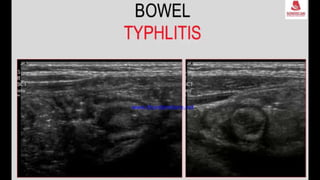

This document discusses the evaluation of right lower abdominal pain and lists appendicitis as a key cause. It notes that other potential causes include hemorrhagic cysts, heterotrophic pregnancy, salpingitis with pyosalpinx, funiculitis, and torsion of an undescended testis. The document was presented by Dr. A.S.M. Sufian of Cumilla Medical College Hospital and thanks the audience for their patience and listening.